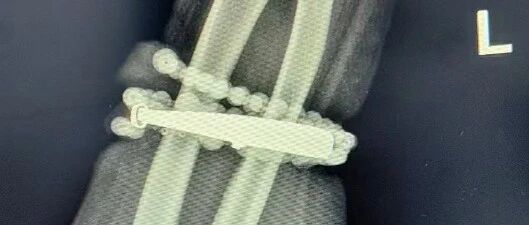

女子手镯10年没摘竟“长”进肉里!医生:再晚点就保不住了